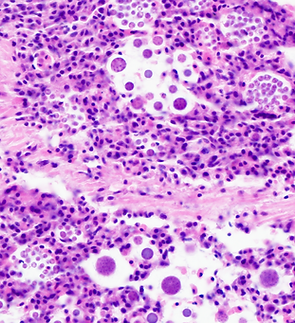

The Aquatic Diagnostic Laboratory offers many different types of diagnostic assays for aquatic organisms, specializing in shellfish and finfish diseases.

We provide disease testing for all life stages, larvae to adult. The type of testing needed is dependent on the host species and pathogens of concern. Please see the descriptions of the diagnostic services offered and submission instructions.